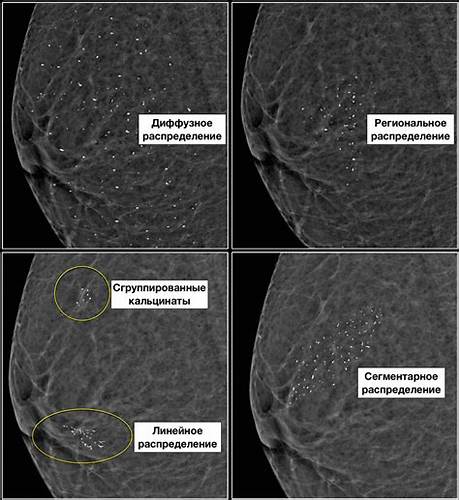

Картинка 29: Доброкачественные заболевания молочной железы - online presentation